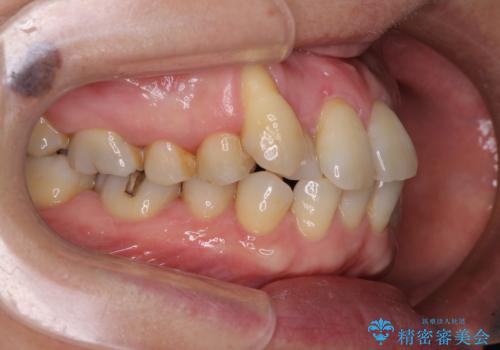

八重歯と形の悪い前歯 矯正治療とセラミック治療

- 長年前歯の歯並びで悩んでいるとのことで来院された患者様です。

機能的なことを考えると八重歯となっている犬歯は抜歯せず、歯列を改善することが望ましいとされますが、数十年もの間犬歯がない咬み合わせで問題なく過ごしてきたため、八重歯を抜歯することで、手っ取り早く歯列を改善することとしました。